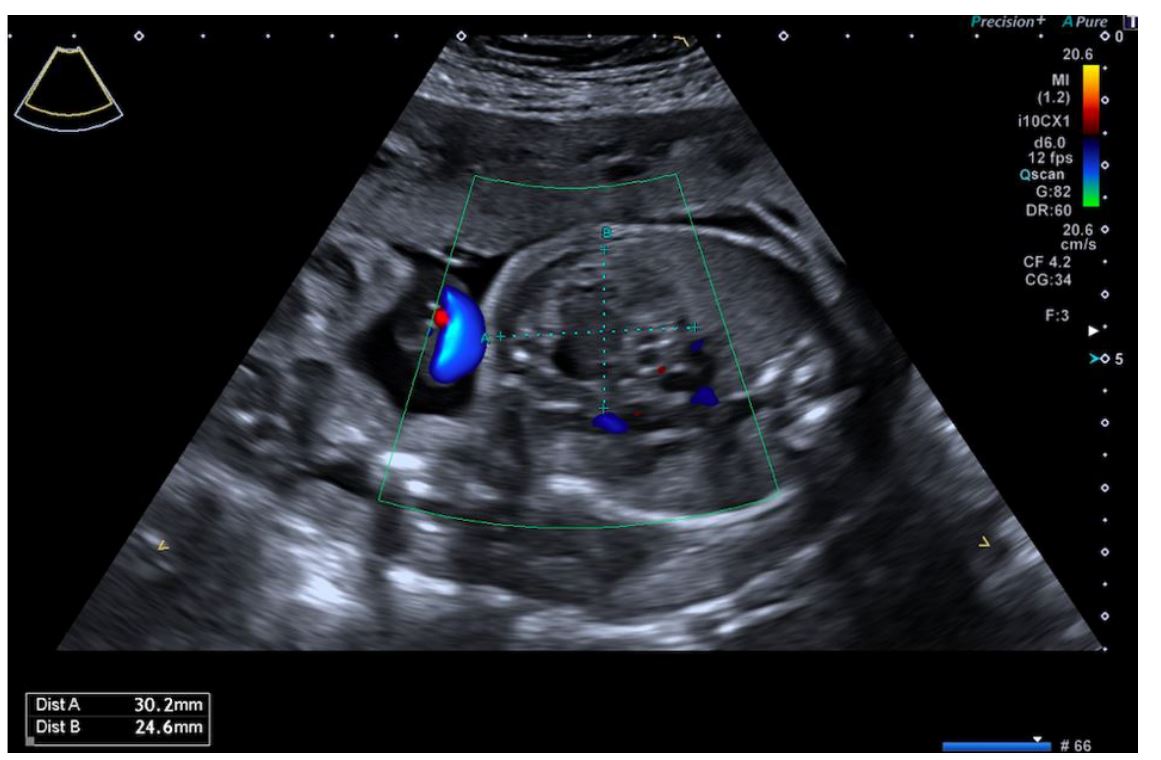

At 25 weeks, a detailed US revealed a heterogeneous mass in the anterior mediastinum measuring 30.2 x 24.6 x 28 mm with cystic and solid components and poor vascularization (Figure 1). Although the mass caused displacement of the mediastinum, there was no evidence of hemodynamic compromise. These findings were consistent with a diagnosis of mediastinal teratoma. Fetal biometry and other anatomic assessments were within normal limits.

Figure 1 Ultrasound at 25 weeks showing a heterogeneous mass located anteriorly and in the midline of the thorax measuring 30.2 × 24.6 × 28 mm with cystic and solid components and poor vascularization.